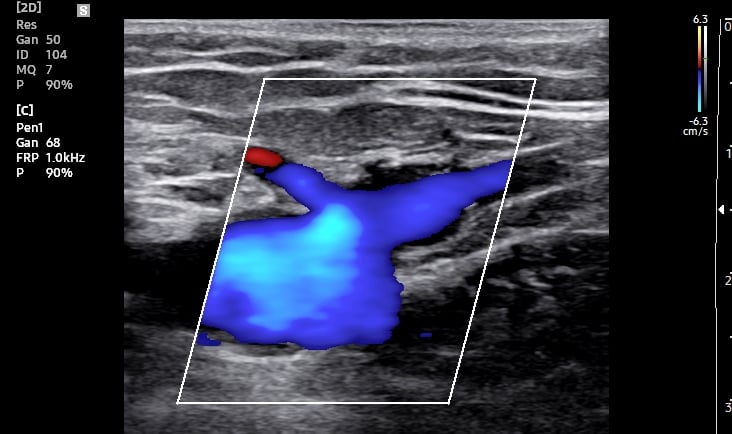

Ultrassom: ondas sonoras criam imagens das veias.

Doppler: identifica a direção e velocidade do sangue (cores no aparelho indicam fluxo normal ou alterado).

O Doppler emite sons e mostra cores no monitor (fluxo sanguíneo).

O Que o Doppler Revela Sobre Suas Varizes?

Mapa Venoso: localização exata das veias doentes.

Grau de Refluxo: se há sangue retornando (principal causa de varizes).

Coágulos (trombose): risco de complicações graves.

Função Valvar: se as válvulas das veias estão funcionando.